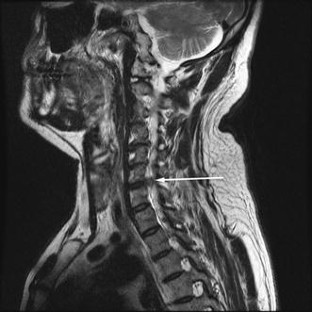

A prospective analysis of the first twenty patients operated for cervical radiculopathy by a new modification of transcorporeal anterior cervical foraminotomy technique. To evaluate early results of a functional disc surgery in which decompression for the cervical radiculopathy is done by drilling a hole in the upper vertebral body and most of the disc tissue is preserved. Earlier approaches to cervical disc surgery either advocated simple discectomy or discectomy with fusion, ultimately leading to loss of motion segment. Posterior foraminotomy does not address the more common anterior lesion. Twenty patients suffering from cervical radiculopathy not responding to conservative treatment were chosen for the new technique. Upper vertebral transcorporeal foraminotomy was performed with the modified technique in all the patients. All the patients experienced immediate/early relief of symptoms. No complications of vertebral artery injury, Horner’s syndrome or recurrent laryngeal nerve palsy were noted. Modified transcorporeal anterior cervical microforaminotomy is an effective treatment for cervical radiculopathy. It avoids unnecessary violation of the disc space and much of the bony stabilizers of the cervical spine. Short-term results of this technique are quite encouraging. Longer-term analysis can help in outlining the true benefits of this technique.

Fig. 1

Fig. 2

Fig. 3

Fig. 4

Fig. 5